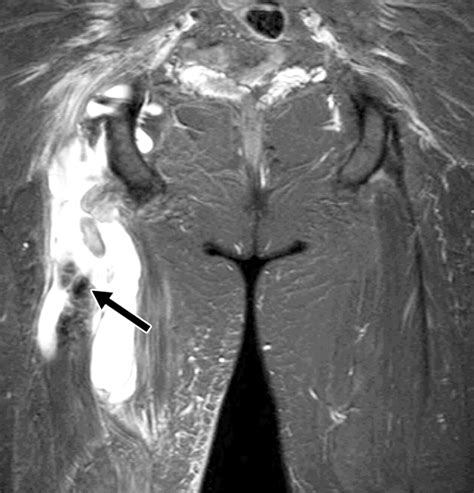

Medical professionals usually rely on a physical examination to diagnose the severity of the tear. In some cases, an MRI may be ordered to visualize the extent of the damage, especially if a surgical repair is being considered. Understanding the timeline is crucial for any recovery plan.